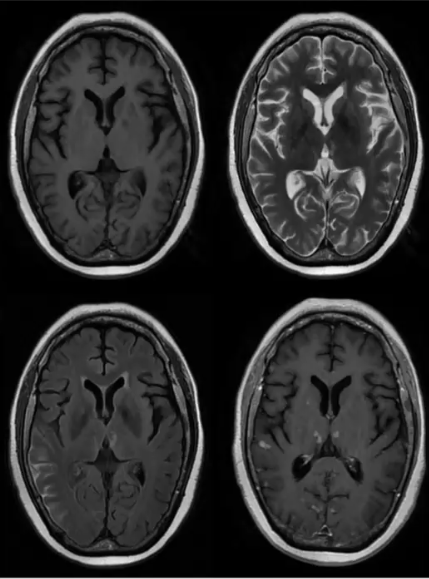

转移瘤

❖ 其CT和MRI表现形态多样,密度和信号也不尽相同,病灶边缘光整,大多伴发不同程度水肿。多有原发肿瘤病史,颅内其他部位有多发病灶存在可提示诊断。

❖ 转移瘤边界多较清,周围水肿为单纯血管源性水肿,无瘤细胞浸润,水肿区血流量因水肿压迫而下降,而恶性胶质瘤周围水肿区伴有肿瘤细胞浸润及伴随的新生血管,常表现为高灌注。因此灌注成像有助于二者的鉴别。